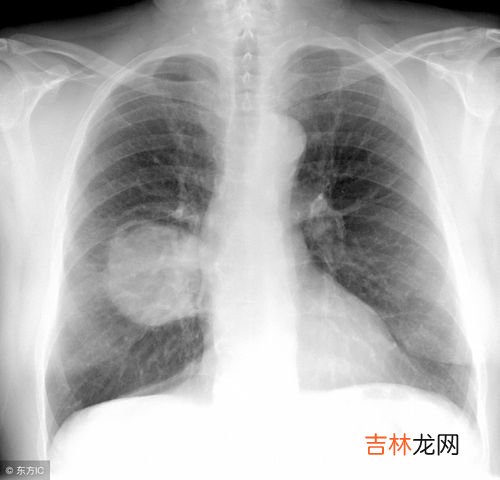

文章插图

间质性肺炎(interstitial pneumonia)是多种原因引起的肺间质炎性和纤维化疾?。?病变主要侵犯肺间质和肺泡腔,包括肺泡上皮细胞、毛细血管内皮细胞、基底膜以及血管、淋巴管周围的组织,最终引起肺间质的纤维化,导致肺泡-毛细血管功能的丧失 。